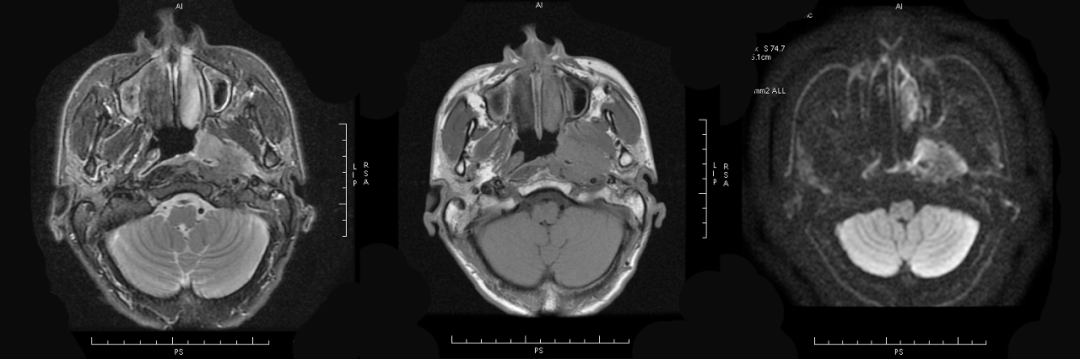

MRI 表现:鼻咽后壁及两侧壁不规则软组织肿块,信号多较均匀,T1WI 像呈等信号,T2WI 像呈稍高信号,DWI 像为明显高信号。增强扫描肿块常轻-中度均匀强化,液化坏死少见。颈部淋巴结肿大常见。肿大淋巴结多边缘规则,内部密度或信号均匀,增强扫描轻度强化。对邻近组织侵犯少,肿块与咽后壁头长肌等分界清楚,多无颅底及相邻骨质破坏。鼻咽部肿块虽较明显,但咽旁间隙较清晰,或只有受压改变。

③MRI 表现为鼻咽顶后部软组织弥漫增厚,通常双侧对称,边界清楚,位于粘膜浅表、咽颅底筋膜的内侧,不累及深层结构,基膜完整,头长肌完好;T1WI 呈中等信号,T2WI 呈均匀中高信号,与正常淋巴组织相同,增强呈中等强化。

MRI 表现:肿瘤与周围组织分界清楚,信号改变类似血供丰富的血管瘤,T1WI 呈中低信号,T2WI 呈中高信号,纤维组织丰富区呈低信号,因此多呈高低混杂信号,多数肿块内可见流空血管影。增强扫描多呈显著不均匀强化。